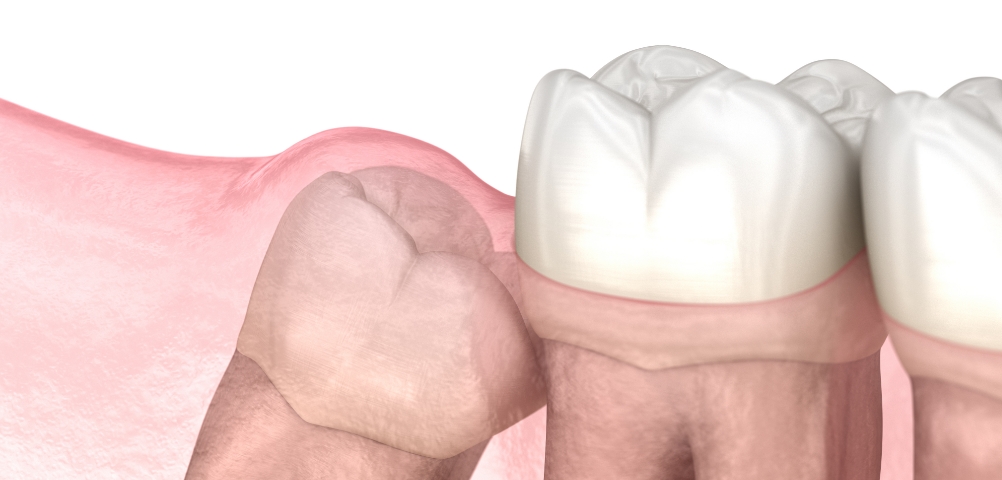

3D CT로 사랑니의 방향, 신경 위치, 주변 치아와의 관계를 세밀하게 확인한 뒤 필요한 경우에 한해 발치를 진행합니다.

불필요한 조직 손상을 최소화하는 방식으로 부담을 줄이며, 환자분이 보다 편안하게 회복하실 수 있도록 돕고 있습니다.